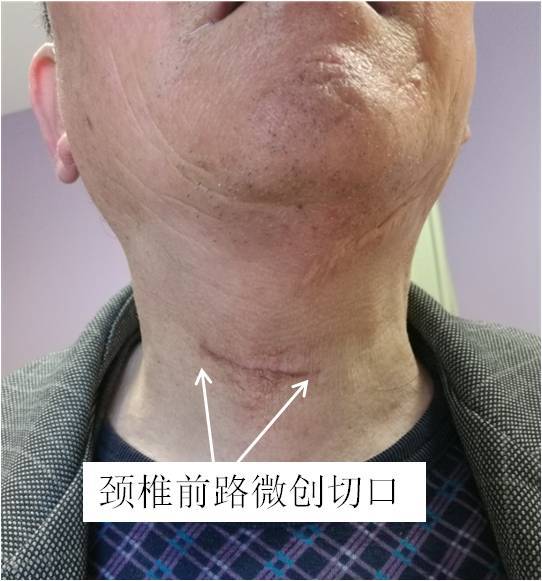

这种手术方式的特点是:手术微创,切口3—4公分(图9),切口美容,出血少(一般100ml),恢复快,术后1—2天可戴颈托下地行走。但对手术的技术要求较高。